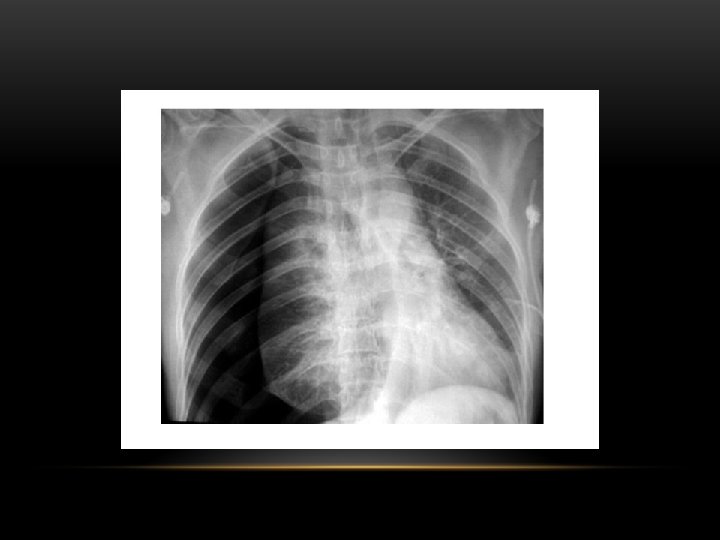

Tension Pneumothorax • No vascular markings on right • Shift of mediastinum to left • Atelectasis right lung • Increased haziness on left: Diversion of entire cardiac output

Tension pneumothorax : is the progressive build-up of air within the pleural space, usually due to a lung laceration which allows air to escape into the pleural space but not to return. Positive pressure ventilation may exacerbate this 'one-way-valve' effect. Progressive build-up of pressure in the pleural space pushes the mediastinum to the opposite hemithorax, and obstructs venous return to the heart. This leads to circulatory instability and may result in traumatic arrest.